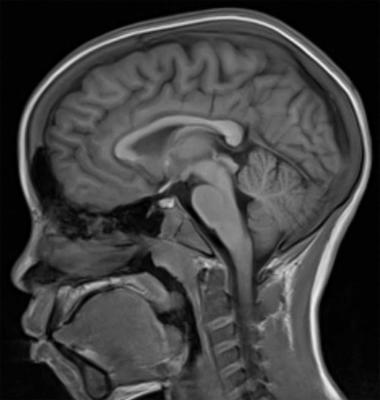

Manyetik Rezonans (MR) cihazları iyonizan radyasyon oluşturmazlar. Oluşturdukları manyetik alan sayesinde görüntü oluşturan bu cihazlar yüksek rezolusyonda anatomik detay verirler. MR cihazında hastanın içine yattığı tünel olan ve magnet adını verdiğimiz büyük bir parça vardır. Bu tünel içerisine yatan hastanın incelenecek bölgesine coil adını verdiğimiz alıcılar bağlanır ve incelemeye bundan sonra başlanır. MR cihazı ile bütün insan vücudu görüntülenebilir. Özellikle beyin ve omurilik hastalıklarında, ortopedik hastalarda özellikle eklem değerlendirmesi için sıklıkla kullanılır. MR görüntüleme teknolojisi de yıllar içinde inanılmaz bir ilerleme göstermiştir.